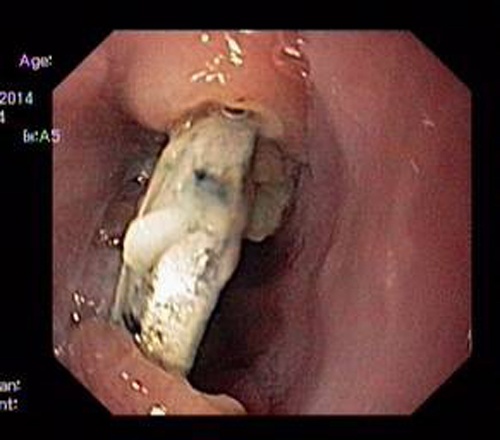

Cuc pin trong thuc quan be trai hinh anh

Cục pin trong thực quản bé trai

0

Bé trai tên L.M.T., 2 tuổi, sống ở quận Long Biên (Hà Nội), đã được gia đình đưa đến Bệnh viện Nhi T.Ư đầu tháng 10 vừa qua do ngạt mũi 4 ngày không đỡ.